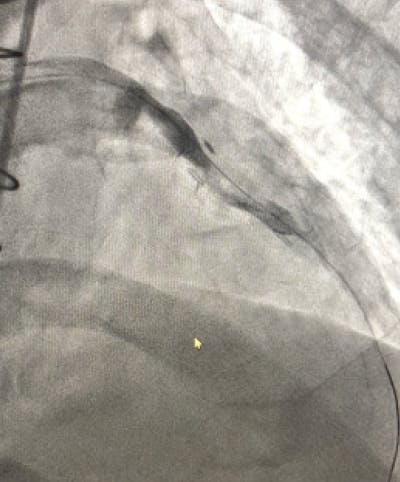

An Impella® device (Abiomed, Inc.) was placed emergently on arrival, and perfusion was restored. The initial angiogram showed an occlusion of the proximal left anterior descending (LAD) artery with an acute cutoff, consistent with thrombosis (Figure 1). The lesion was wired with a 0.014-inch balance middleweight wire (BMW; Abbott). CAT RX was used frontline, and flow was restored after two passes with 30 seconds of aspiration (Figure 2). The door-to-device time was 45 minutes. After mechanical thrombectomy, intravascular ultrasound was performed, revealing evidence of plaque rupture and minimal associated plaque burden. Primary stent implantation was therefore performed with a 3- X 28-mm DES, which was postdilated with a 3.25-mm noncompliant balloon to 18 atm. Final angiography revealed TIMI 3 flow with no evidence of distal embolization and restoration of myocardial blush (Figure 3). The Impella® device was removed at the end of the procedure. The patient experienced a full recovery and was discharged from the hospital after 3 days.

Figure 2. Flow through LAD after mechanical thrombectomy with CAT RX.

Figure 3. Final angiogram showing TIMI 3 flow through the vessel.